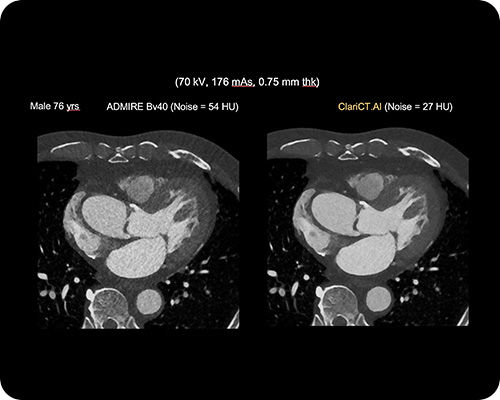

ClariCT.AI

AI-Powered Radiation Reduction

The first AI software that dramatically reduces radiation exposure while delivering the highest quality CT images using advanced AI denoising technology.

Reduces radiation exposure by 70-95% while maintaining superior image quality